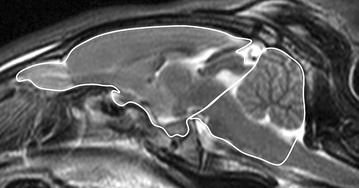

Fig. 1.

Mid-sagittal T2w image of the rabbit brain: the midline area of the caudal cranial fossa was defined as the area limited caudally by the foramen magnum and cranially by the rostral contour of the cerebellum and the dorsum sella turcica. The midline area of the cranial cranial fossa included the olfactory bulb, following the dorsal brain surface until the caudal pole, then following the tectum mesencephali to the dorsum sella turcica, going rostrally to the olfactory bulb again, including the pituitary gland and the optic chiasm